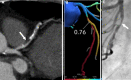

Myocardial ischemia is caused by a mismatch between myocardial oxygen consumption and oxygen delivery in coronary artery disease (CAD). Stratification and decision-making based on ischemia improves the prognosis in patients with CAD. Non-invasive tests used to evaluate myocardial ischemia include stress electrocardiography, echocardiography, single-photon emission computed tomography, and magnetic resonance imaging. Invasive fractional flow reserve is considered the reference standard for assessment of the hemodynamic significance of CAD. Computed tomography (CT) angiography has emerged as a first-line imaging modality for evaluation of CAD, particularly in the population at low to intermediate risk, because of its high negative predictive value; however, CT angiography does not provide information on the hemodynamic significance of stenosis, which lowers its specificity. Emerging techniques, e.g., CT perfusion and CT-fractional flow reserve, help to address this limitation of CT, by determining the hemodynamic significance of coronary artery stenosis. CT perfusion involves acquisition during the first pass of contrast medium through the myocardium following pharmacological stress. CT-fractional flow reserve uses computational fluid dynamics to model coronary flow, pressure, and resistance. In this article, we review these two functional CT techniques in the evaluation of myocardial ischemia, including their principles, technology, advantages, limitations, pitfalls, and the current evidence.